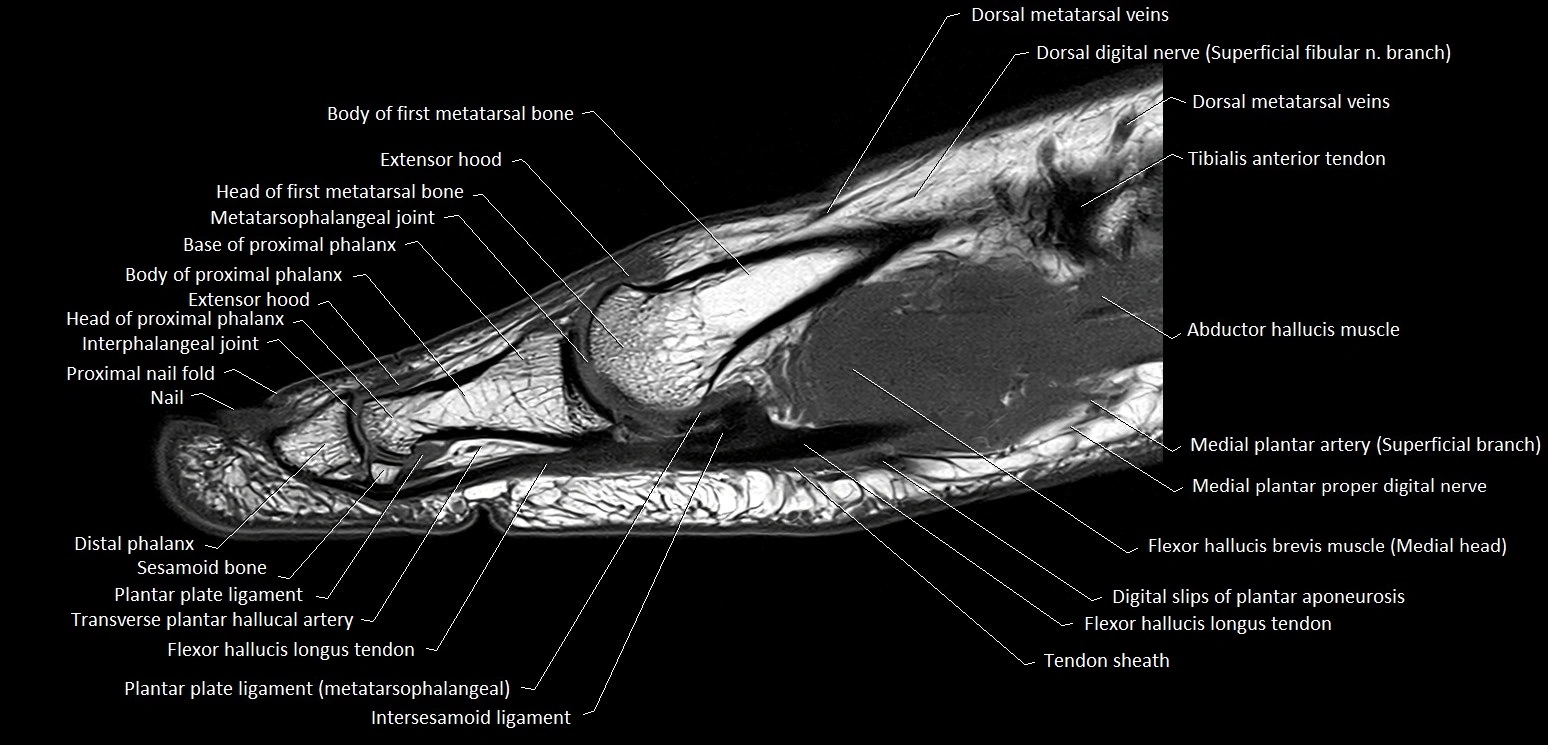

MRI image

image